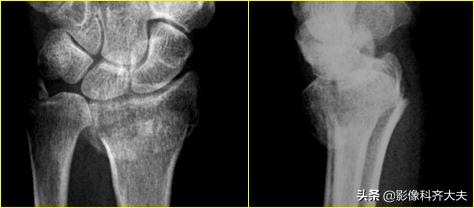

肱骨远端骨折后大量骨痂形成,骨小梁穿越骨折处